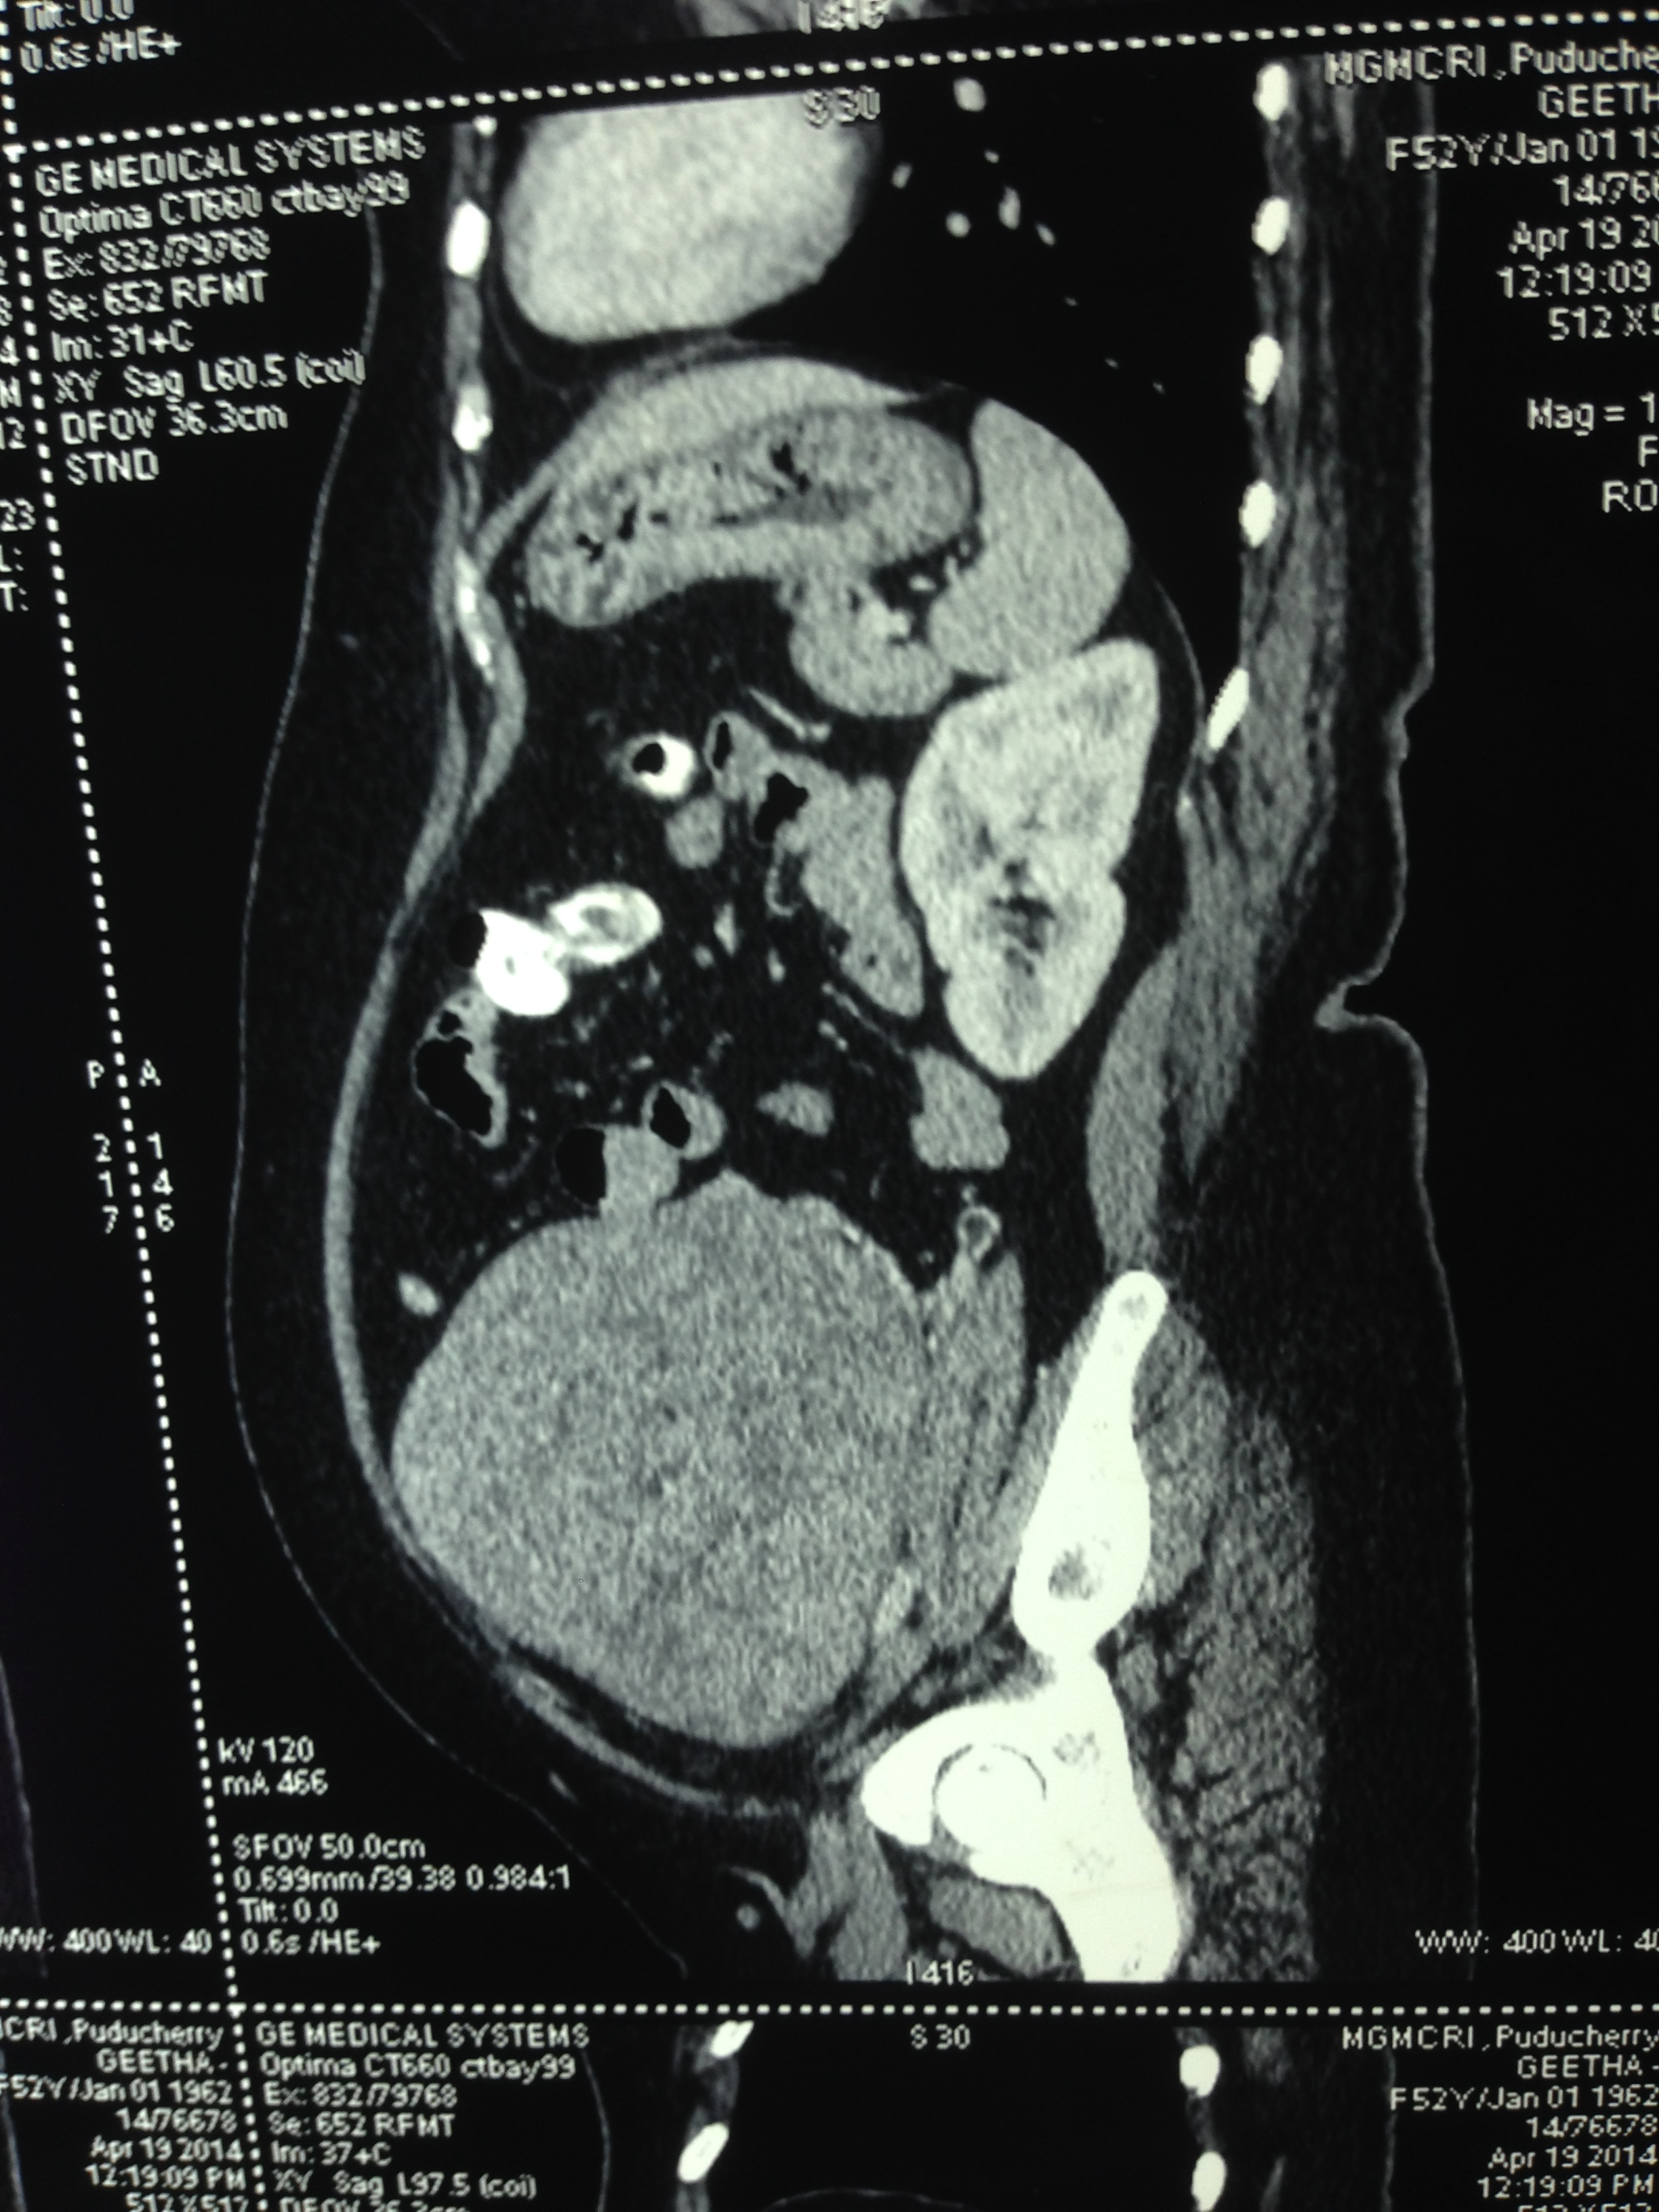

So a CT scan was done next . These pictures are reproduced here using a cell phone’s camera.

The following picture shows the enlarged uterus and large sub serous myomas extending upto the liver.

The large sub serous fibroids are seen below.

Enlarged uterus with leiomyoma with mucinous and cystic degeneration and adenomyosis and two large sub serous fibroids arising from the fundal and right lateral aspect undergoing hyalinisation.